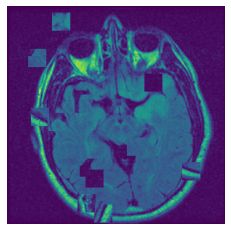

In figure 3, we present qualitative examples of different masking strategies. It is observed that, unlike context prediction and restoration, our method tends to propose targeted masks like the tumor regions or regions with abnormalities and avoids masking less helpful regions. However, it should be noted that Intelligent-Masking does not necessarily mask the tumor regions but considers all areas of interest that results in better feature learning. Examples of other masking samples are provided in supplementary materials. Furthermore, in medical images, unlike natural scenes, the structures are very local with imbalanced information throughout an image. Therefore, random masking strategies as shown in Fig 3 operate ineffectively by masking non-informative regions.

Figure 2: Qualitative examples of compared method’s strategies for masking

Figure 3: More qualitative examples of different distorting strategies including our method. We show the different self-supervised mechanisms on both datasets of MR (rows: 1-3) and ultrasound (rows: 4-6) images for lower-grade glioma and breast cancer diagnosis respectively. We include both images of normal (rows: 1,4) and cancer (rows: 2,3,5,6) conditions for each dataset. We also observe that our method treats each image based on its context information with no predetermined strategy.